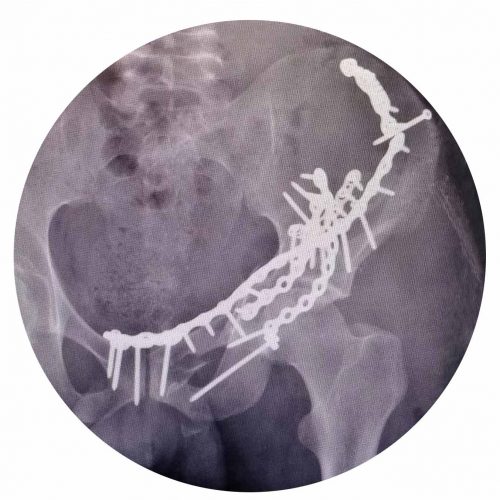

Acetabulum and Pelvic Ring Osteosynthesis

Surgical fixation of this type of fracture is complex, laborious and not without risk due to the proximity of important anatomical structures, so they must be performed by specialists in pelvic and hip trauma. Fixation is done with plates and screws.